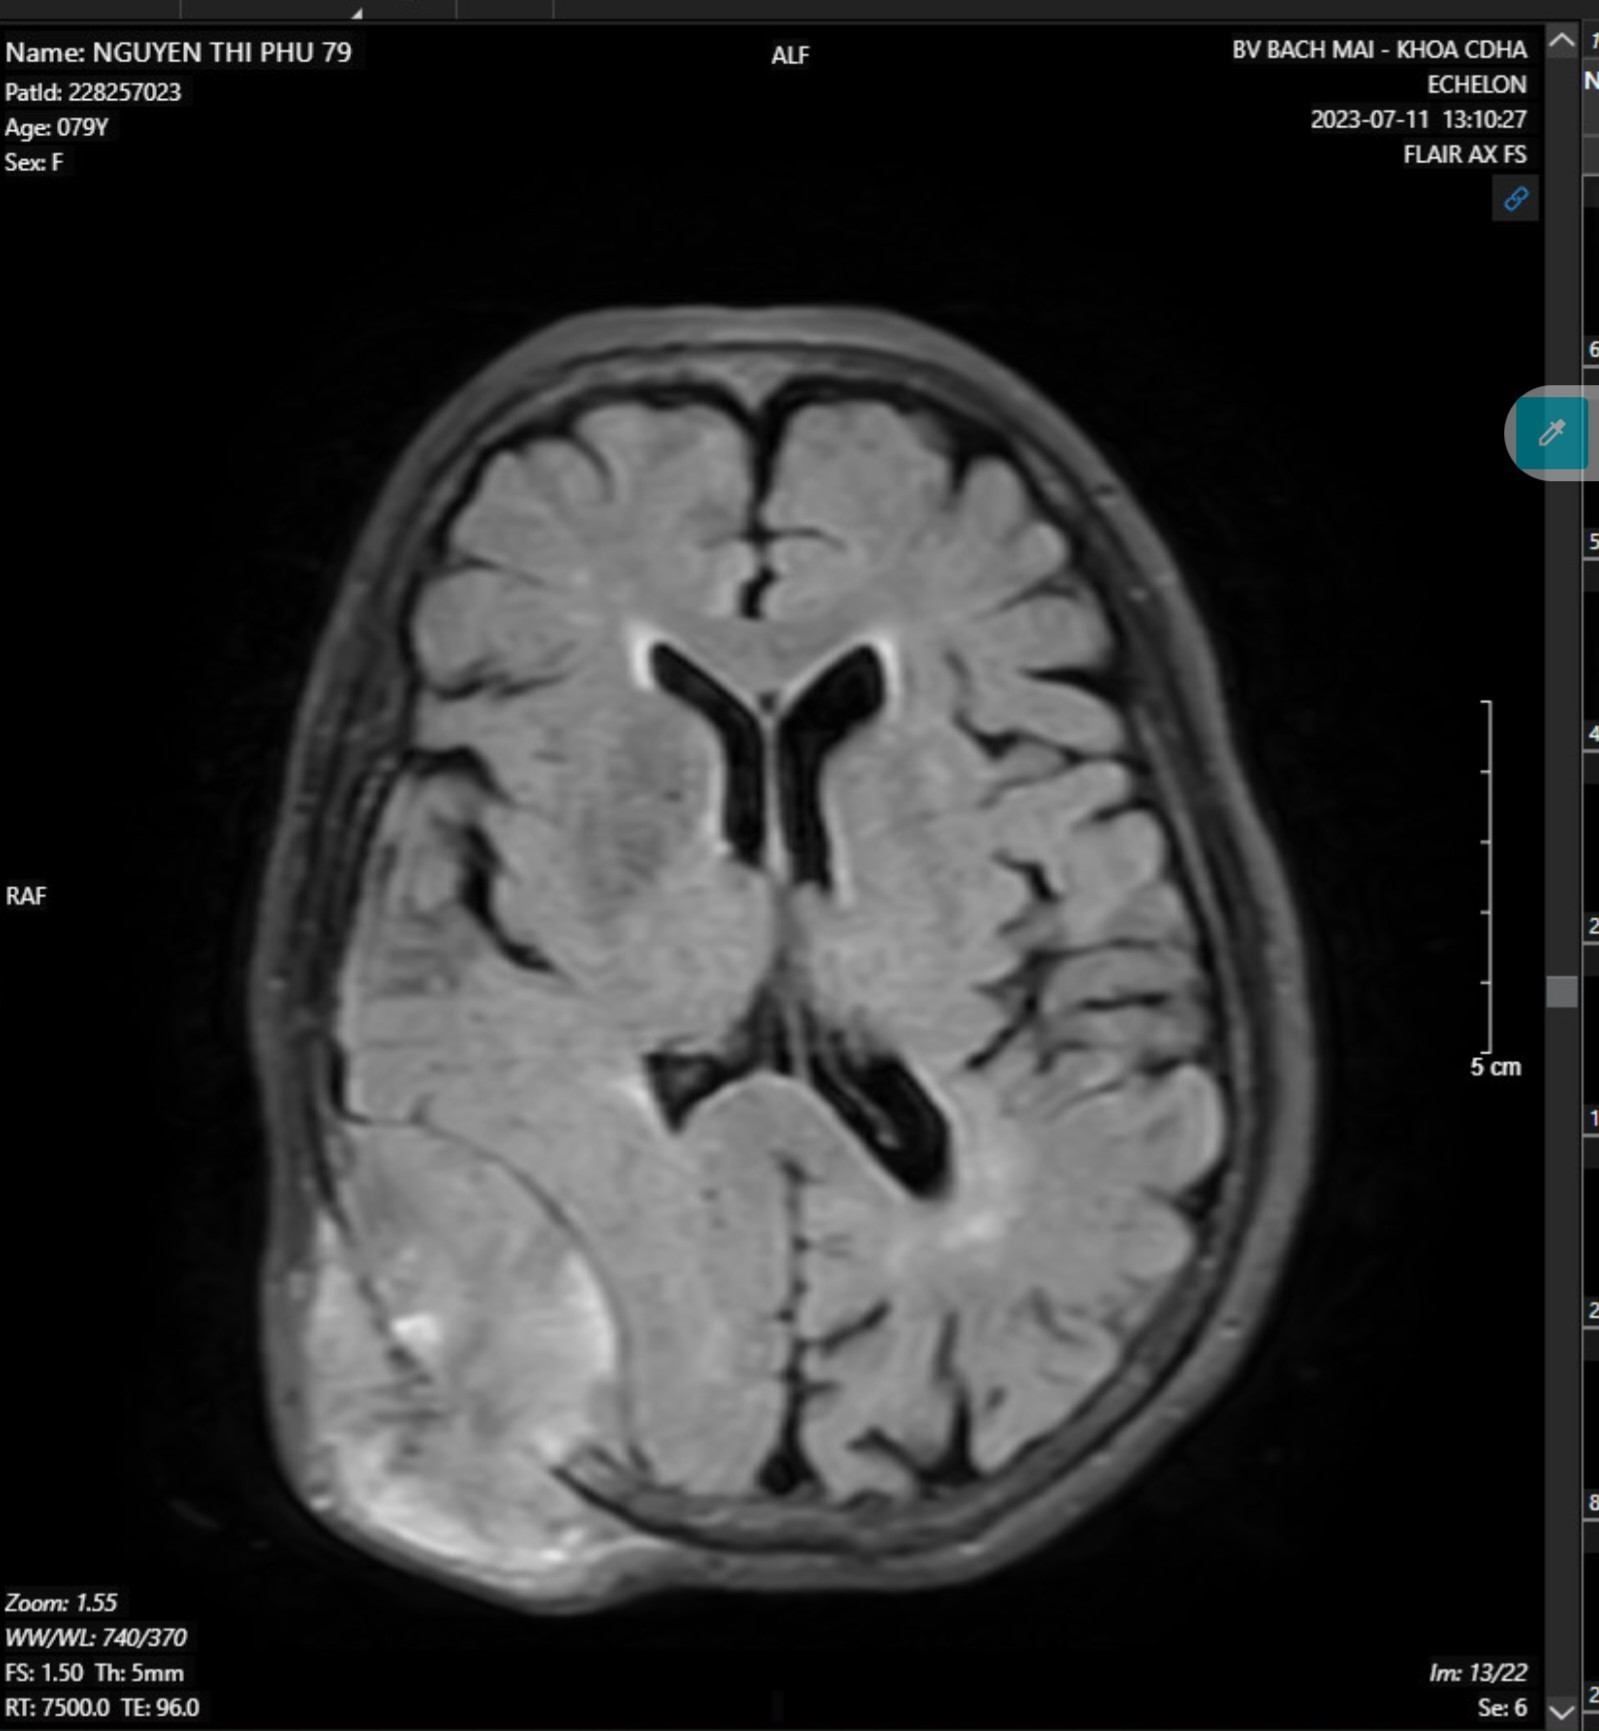

- MRI não-mạch não có tiêm thuốc đối quang từ:

Hình ảnh khối ngoài trục vùng thái dương-chẩm phải kích thước 48x50x60mm nghĩ nhiều đến khối u xương, có chảy máu trong u, gây tiêu xương sọ và xâm lấn phần mềm

Hình 2. Hình ảnh MRI não-mạch não có tiêm thuốc đối quang từ.